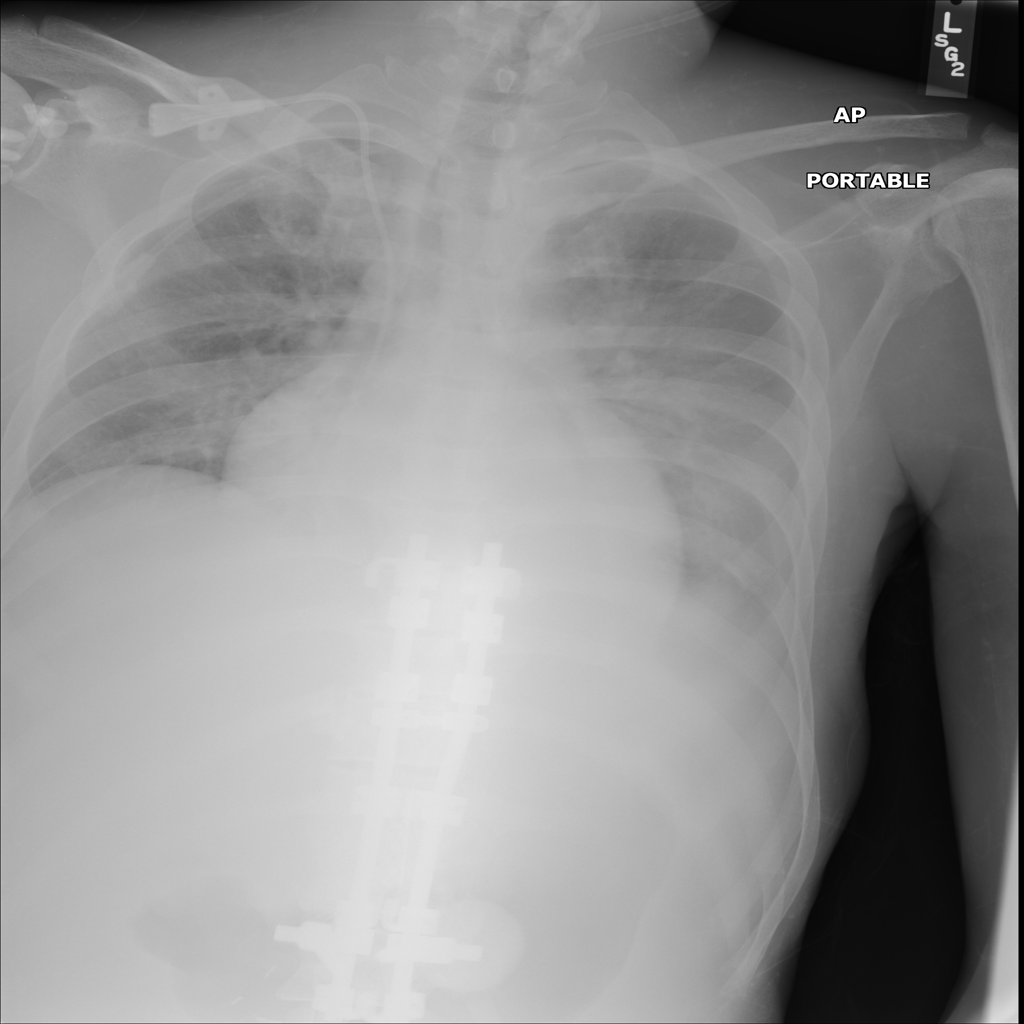

PAT-64EB · IMG-015Consolidation

PAT-64EB · IMG-015

AP